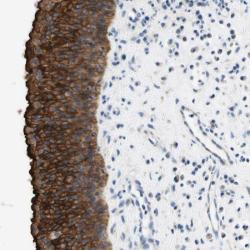

Supportive validation

- Experimental details

- Immunohistochemical staining of human nasopharynx shows strong cytoplasmic positivity in respiratory epithelial cells.

- Validation comment

- Staining pattern partly consistent with experimental and/or bioinformatic data.